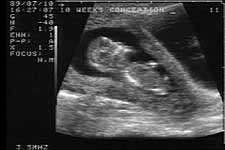

10 week 2 D ultrasound

Kori, 26, who was having her third abortion, asked to watch the procedure on the ultrasound monitor. “I wanted to see what it was like,” she said. “It was O.K. to watch. Once you had your mind made up to do it, you just suck it up and go with it.”